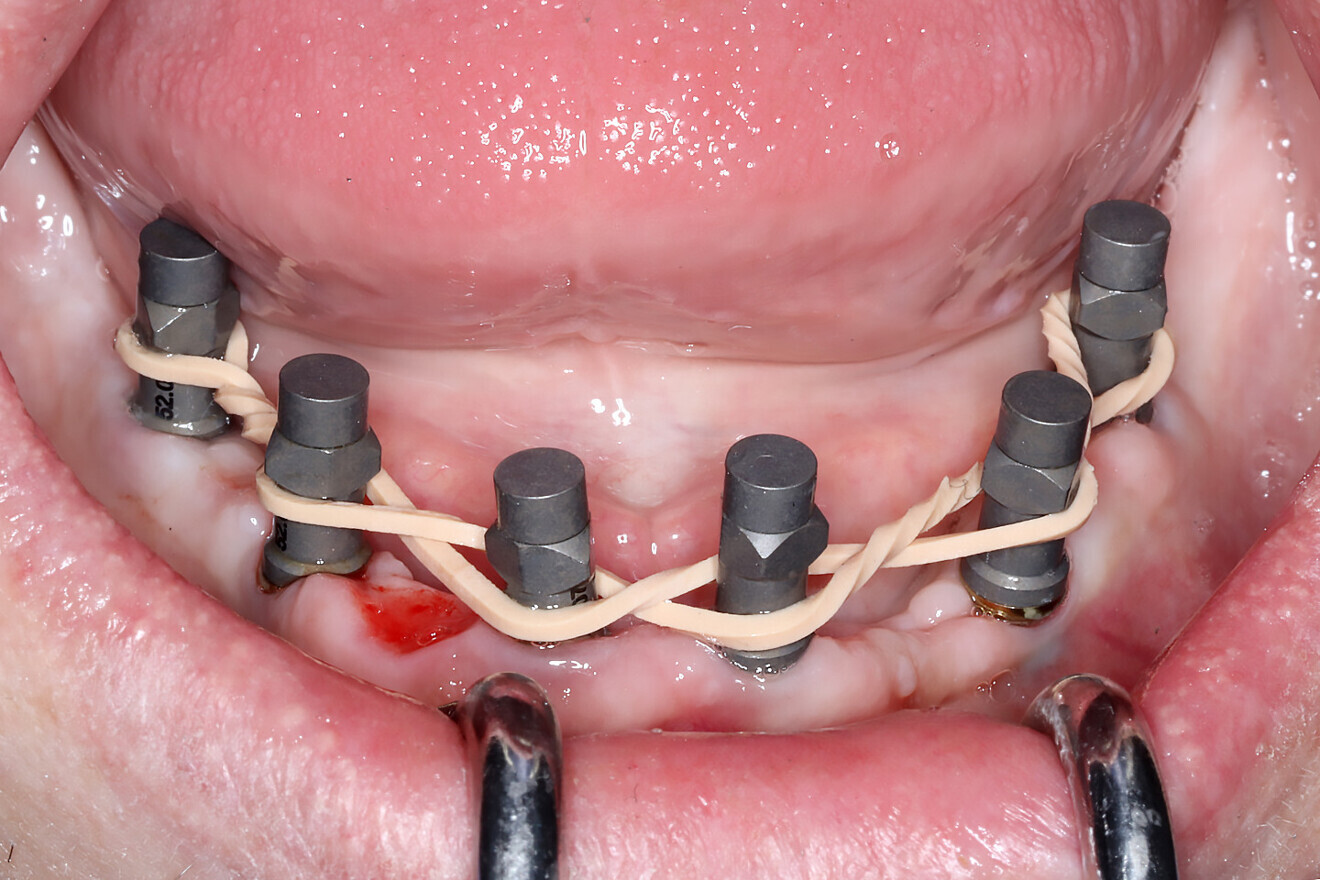

IOS technology requires a stable environment for data to be stitched and captured accurately. Several techniques have emerged to aid the clinician in scanning these difficult environments, characterised by improper retraction, salivary flow, lack of stable keratinised soft tissue and large distances between scanned objects. The splinting of scan bodies with elastic bands or wires (Figs. 1a & b), for example, has facilitated the ability of scanners to continue a scan without interruption by creating a linear path for data capture.5 Innovative techniques such as the sigma composite curve (Fig. 1c) and fiducial markers fixated to the bone have also helped improve the scanning flow.6 While these processes work for some and not for others, developers have created alternative workflows to aid in the acquisition of accurate intra-oral data.

Figs. 1a–c: Rubber bands (a & b) or composite applied directly to the tissue (c) to aid intra-oral scanners in acquiring accurate data.